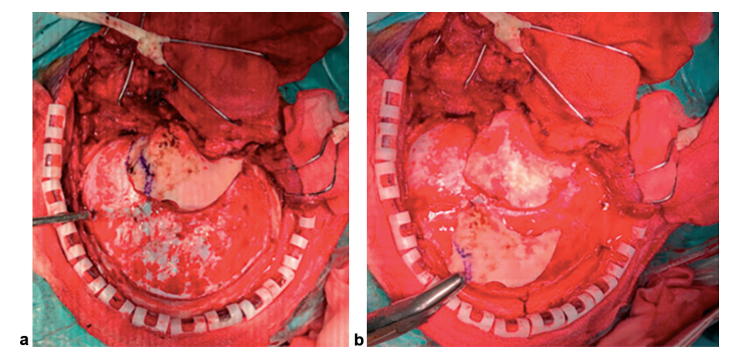

小脑幕切口:小脑幕通过颞下硬膜切口切开,平行于SPS,距SPS 1.5cm,延伸至裂孔。距SPS 1.5cm是安全的,可以避免进入静脉腔隙。剪开小脑幕前必须对CN IV进行识别和保护。

图3.(a)小脑幕及切口位置示意图(CS,海绵窦;SPS,岩上窦;SS,乙状窦;TS,横窦)。(b)颞下小脑幕切口显微视图。切开小脑幕前务必识别滑车神经。